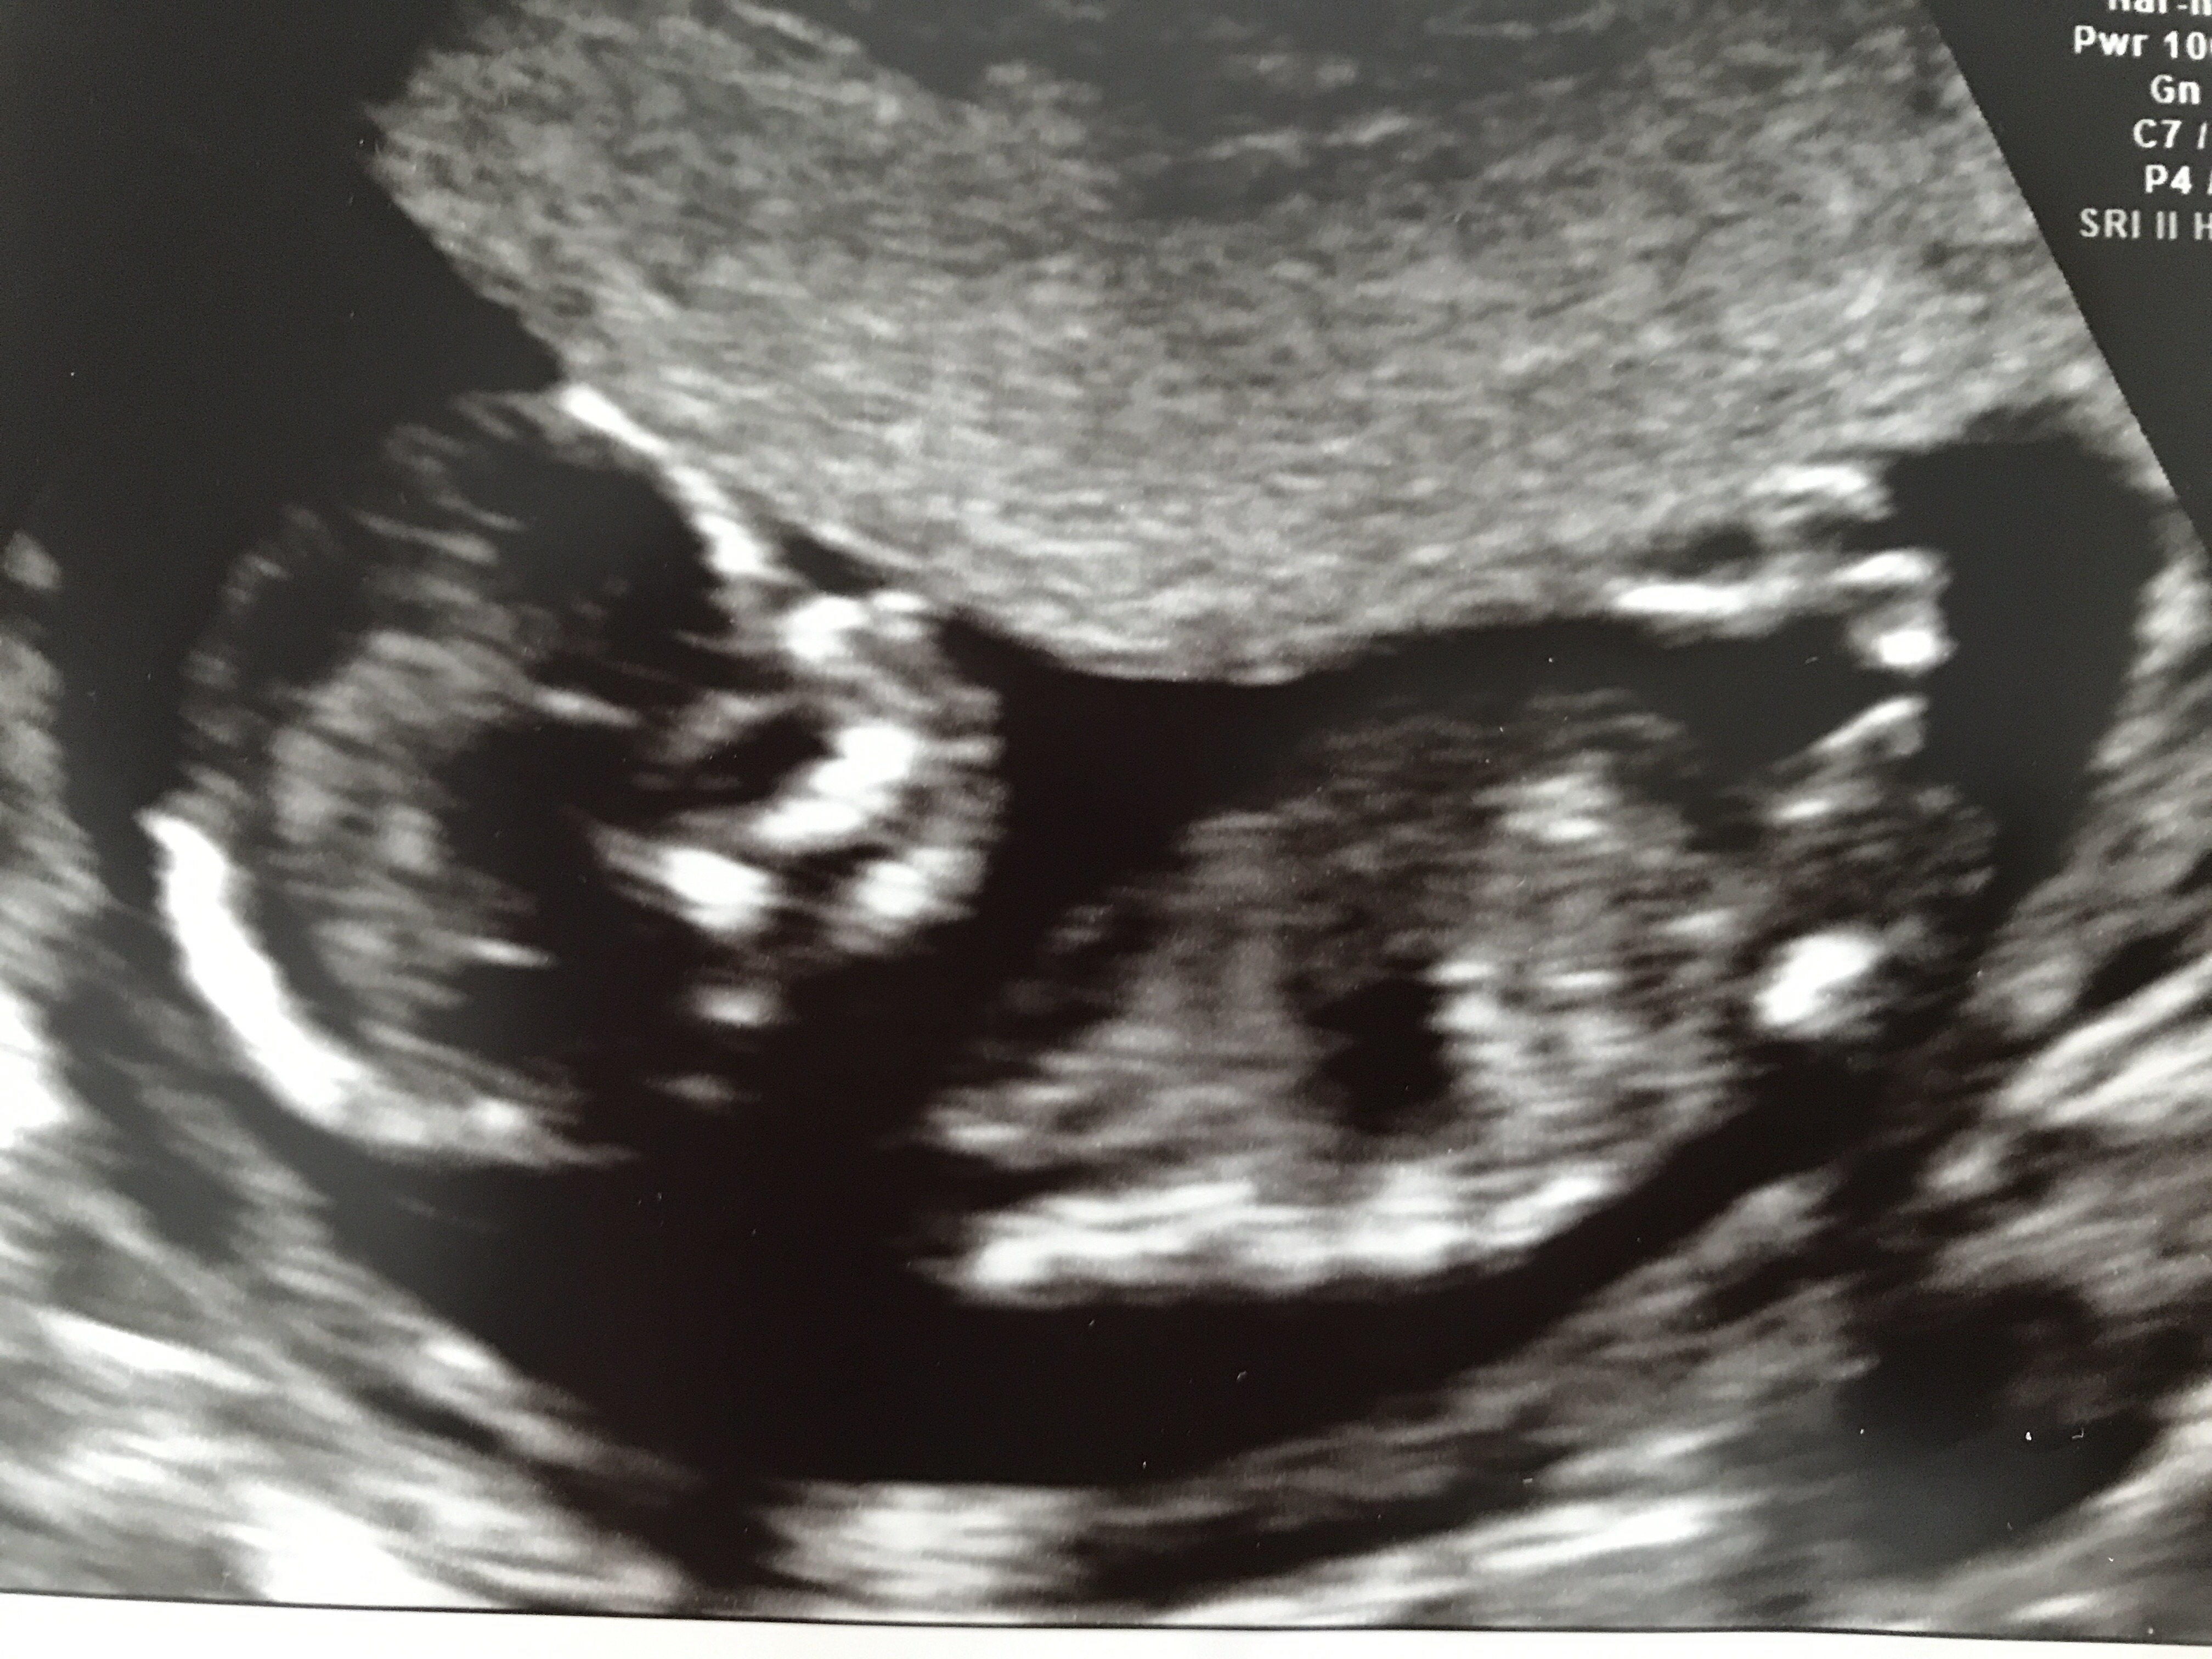

I'm still getting my head around these theories and I'm not particularly good at predicting the gender from my scans, so I'd really appreciate any predictions you have. I'll upload my scans taken at 14w 4d.

Attachment 36769